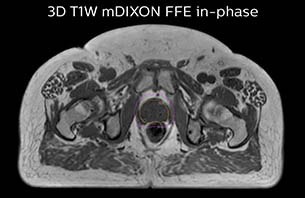

MR-only based planning for prostate cancer radiation therapy treatment

A 77-year-old male with prostate cancer cT3aN0M0, Gleason 8 and PSA 52 μg/L referred to androgen deprivation and radiation therapy with a prescribed dose of 50 Gy to the pelvic lymph node regions and 76 Gy to the prostate.

Turku MRI-T1W therapy case 1

The 3D T1W FFE mDIXON sequence provides in-phase, water and fat images in one acquisition. Target and organs-at-risk are delineated on the 3D T2W TSE images. Prostate GTV is shown in orange, PTV in purple. The 3D bFFE sequence is used by the planner to mark the position of the fiducial markers (gold anchors) and contours are transferred to the digitally reconstructed radiographs (DRRs).